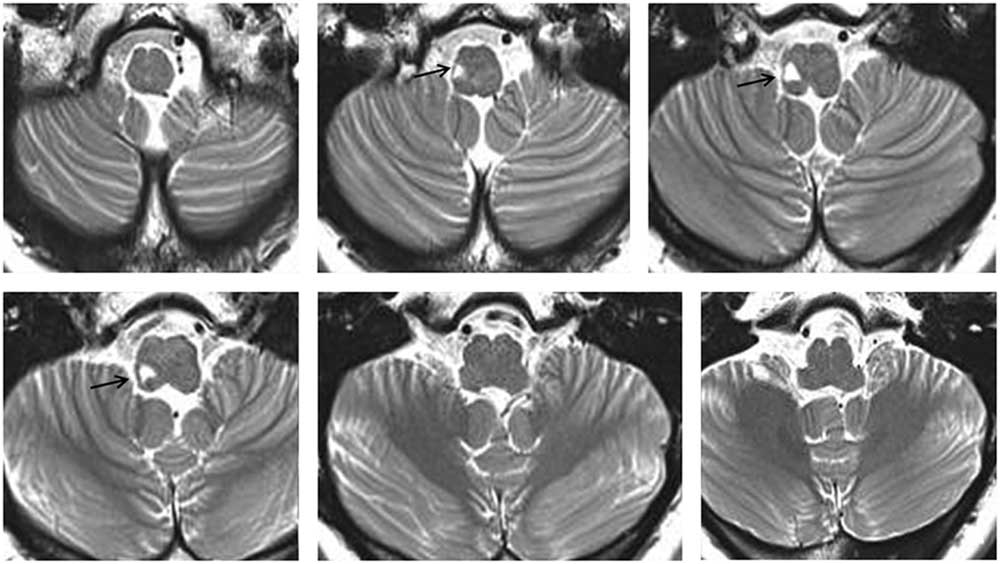

A 44-year-old woman with right LMI was referred for evaluation of oscillopsia and imbalance for 8 months (Figure 1). The oscillopsia was most severe during rightward gaze. She also reported intermittent diplopia and a feeling of tumbling due to upside-down reversal of vision, mostly in the morning. Previous medical records described severe vertigo and imbalance along with left-beating horizontal-torsional nystagmus, right Horner syndrome, and decreased pain and temperature sensation in the right face and left side of the body during the acute phase. Examination at the time of consultation 8 months later additionally showed rightward head tilt and right hypotropia of 5 prism diopters. The spontaneous nystagmus had been changed into ipsiversive torsional (the top poles of the eyes beating toward the right ear) and downbeat. While the intensity of torsional nystagmus was similar in both eyes, the downbeat nystagmus was greater in the hypotropic right eye (Figure 2A). The nystagmus increased without fixation and during rightward gaze. Horizontal head-shaking for 10 seconds induced vigorous right-beating nystagmus and leftward truncal pulsion (see Video). Ipsilesional saccades were hypermetric. Horizontal smooth pursuit was impaired to the right, and vertical smooth pursuit was intruded by nystagmus. Fundus photography showed rightward ocular torsion (Figure 2B, normal range = 0–12.6°; positive values indicate an excyclotorsion), even though the degrees varied due to continuous torsional nystagmus. However, the subjective visual vertical was within the normal range (2.8° with right-monocular viewing, 2.6° with left-monocular viewing, 1.4° with binocular viewing; normal range=–3.1°~–3.0°; positive values indicate rightward torsion from the patient’s perspective). The initial and follow-up magnetic resonance images (MRIs) at the time of consultation showed an infarction restricted to the caudal and middle portions of the right lateral medulla without interval changes (Figure 1). The oscillopsia, nystagmus, and imbalance persisted over the following two years without a response to gabapentin up to 2,700 mg per day.

Figure 1 T2-weighted MRIs show a focal high signal intensity lesion involving the right lateral medulla (arrows).

The evolution of spontaneous nystagmus in our patient may indicate a shift in the vestibular imbalances from initial disruption into late disinhibition and resultant excitation of the vestibulo-ocular reflex pathways. Excitation of the anterior semicircular canal (AC) induces the VOR in the upward and contraversive torsional directions by activating the ipsilateral superior rectus and contralateral inferior oblique muscles via the superior vestibular nucleus (SVN).Reference Ito, Nisimaru and Yamamoto 5 Since the flocculus and paraflocculus selectively inhibit the AC pathway, damage to these inhibitory fibres and resultant activation of the AC pathway would generate nystagmus beating downward and contraversive. The MRIs of our patient showed an infarction restricted to the caudal and middle portions of the right lateral medulla, sparing the rostral area harbouring the SVN. Accordingly, the late torsional-downbeat nystagmus may be explained by relative activation of the ipsilesional AC pathway from disinhibition, probably due to disruption of the inhibitory fibres from the cerebellum or contralateral vestibular nuclei. Repetitive stimulations of the SVN also primarily induced torsional-downbeat nystagmus in rabbits.Reference Ito, Nisimaru and Yamamoto 5 Otherwise, the torsional-downbeat nystagmus may be explained by a combination of torsional nystagmus from the lateral medullary lesionReference Morrow and Sharpe 1 and downbeat nystagmus from damage to the paramedian tract neurons.Reference Wagner, Lehnen and Glasauer 6